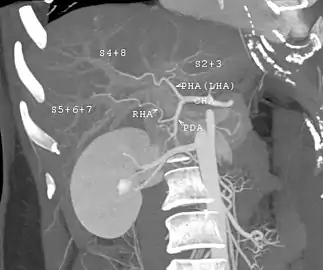

With the recent advances of noninvasive imaging, living liver donors usually have to undergo imaging examinations for liver anatomy to decide if the anatomy is feasible for donation. The evaluation is usually performed by multidetector row computed tomography (MDCT) and magnetic resonance imaging (MRI). MDCT is good in vascular anatomy and volumetry. MRI is used for biliary tree anatomy. Donors with very unusual vascular anatomy, which makes them unsuitable for donation, could be screened out to avoid unnecessary operations.

MDCT image. Arterial anatomy contraindicated for liver donation